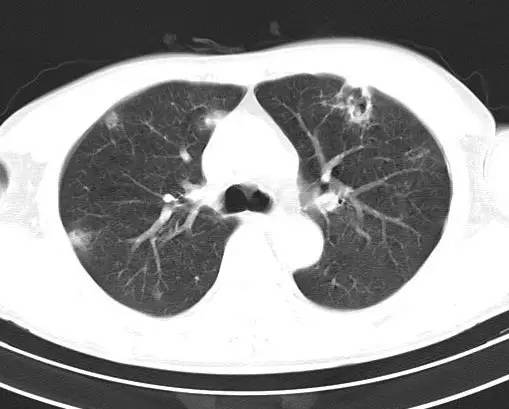

治疗前CT(图1-8):两肺胸膜下散在多发斑片状、结节状伴空洞影,边缘欠清晰。